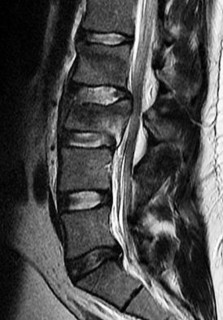

Question 22:

A 54-year-old male with a history of intravenous drug use presents with severe back pain, fever, and progressively worsening bilateral lower extremity weakness over the last 48 hours. A representative MRI is shown below. Given the classic findings for this pathology, what is the most likely causative organism, and what is the standard definitive treatment?

Correct Answer: Staphylococcus aureus; urgent surgical decompression and targeted antibiotics

Explanation:

The clinical scenario and presumed MRI findings (epidural fluid collection causing cord compression) are classic for a spinal epidural abscess. The most common causative organism overall, and specifically in intravenous drug users, is Staphylococcus aureus. Because the patient is exhibiting progressive neurologic deficits (lower extremity weakness), urgent surgical decompression (usually a laminectomy) combined with targeted intravenous antibiotics is the standard definitive treatment to prevent permanent neurologic injury.

A 62-year-old male of East Asian descent presents with progressive myelopathy. His imaging is shown. Which of the following specific CT findings is the strongest independent predictor of a dural tear during an anterior cervical corpectomy and decompression for this condition?

Options:

Correct Answer: The 'double-layer' sign

The image indicates Ossification of the Posterior Longitudinal Ligament (OPLL). The 'double-layer' sign on a CT scan is highly specific for dural ossification and represents a significant risk for dural tears during anterior decompressive surgeries. It consists of anterior and posterior hyperdense ossified rims separated by a central hypodense non-ossified ligament.